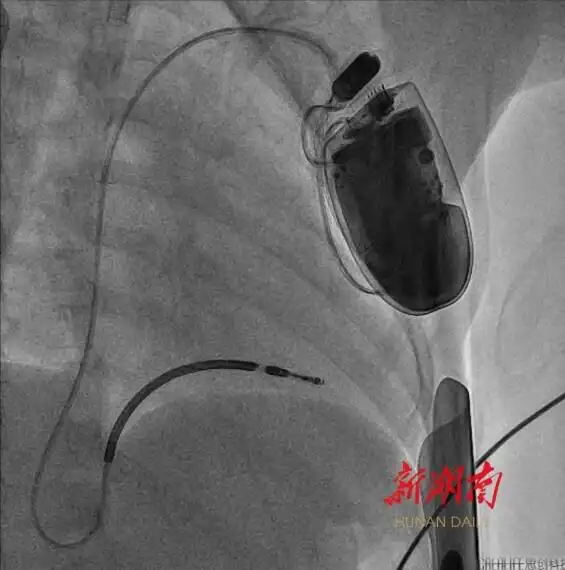

湖南日報4月22日訊(文字/視頻 全媒體記者 周陽樂 通訊員 黃娟 宋青青)今天,記者從湖南省兒童醫(yī)院獲悉,該院血管內(nèi)科陳智主任團(tuán)隊近期成功為一名年僅4歲半、體重16公斤的短QT間期綜合征患兒植入心臟轉(zhuǎn)復(fù)律自動除顫器(ICD)。此為中南地區(qū)年齡最小、體重最低的兒童心臟轉(zhuǎn)復(fù)律自動除顫器手術(shù)案例。

體重輕、血管細(xì)小、皮下脂肪薄……術(shù)前,團(tuán)隊對手術(shù)路徑設(shè)計、導(dǎo)管操作方式、麻醉方案及術(shù)中突發(fā)狀況處理等細(xì)節(jié)進(jìn)行了嚴(yán)密論證。4月16日上午,在麻醉師全程監(jiān)護(hù)下,團(tuán)隊結(jié)合血管超聲的特點,成功經(jīng)腋靜脈,將電極導(dǎo)線精準(zhǔn)送達(dá)右心室心尖部,并通過調(diào)整預(yù)留適合孩子生長的長度,經(jīng)程控測試確認(rèn)最佳起搏閾值后,與ICD裝置完成精準(zhǔn)連接。